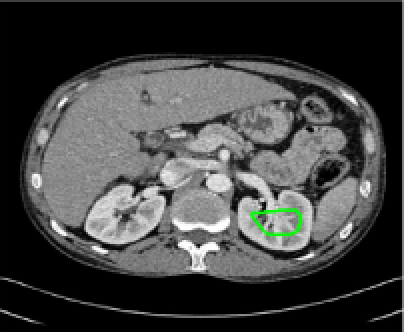

Four sets of test results are shown below. In Test 1 we compare models M1 – M6 to the proposed model M7 for two images which are hard to segment. The first is a CT scan from which we would like to segment the lower portion of the heart, the second is an MRI scan of a knee and we would like to segment the top of the Tibia. See Figure 9 for the test images and the marker sets used in the experiments. In Test 2 we will review the sensitivity of the proposed model to the main parameters. In Test 3 we will give several results achieved by the model using marker and anti-marker sets. In Test 4 we show the initialisation independence and marker independence of the Geodesic Model on real images.

Refer to captionRefer to captionRefer to captionRefer to caption

(i)                                 (ii)                                 (iii)                                 (iv)

Figure 9: Test 1 setting: (i) Image 1;  (ii) Image 1 with marker and anti-marker set shown in green and pink respectively;  (iii) Test Image 2; (iv) Image 2 with marker set shown.